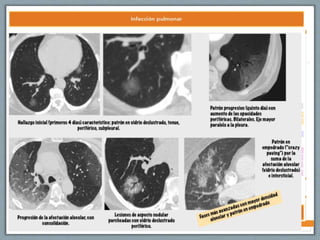

• #19 Chest radiograph of a patient with influenza-related pneumonia that illustrates early ALI, which progressed over 48 hours to more classic ALI that required positive-pressure ventilation. (A) Anterior-posterior portable chest radiograph of a previously healthy 41-year-old man who presented to the emergency department with a 2-day history of myalgias and fever, a productive cough, and shortness of breath. Chest auscultation revealed rales and rhonchi posteriorly in both lung fields. The chest radiograph demonstrates patchy infiltrates in the right lower lung field and also in the left lower lung field. (B) Anterior-posterior chest radiograph 48 hours after the chest radiograph in A, 1 hour after endotracheal intubation (arrow) and initiation of positive-pressure ventilation using the ARDS Network lung-protective ventilation protocol (97). There was marked progression of the bilateral radiographic infiltrates, with dense consolidation in the right upper, right lower, and left lower lung zones. The patient’s hypoxemia steadily worsened during the 48 hours following his initial presentation, accompanied by an increase in respiratory rate to 40 breaths/minute. Diagnostic evaluation confirmed H1N1 influenza infection. All cultures for bacteria were negative. Recent clinical investigation indicates that it is possible in some patients to diagnose ALI in an early phase (9), as shown in A, well before the progression of acute respiratory failure to the need for mechanical ventilation, as illustrated in B. Earlier diagnosis of ALI could facilitate testing of therapeutic strategies that may have time- dependent efficacy prior to the development of established ALI that requires intubation and mechanical ventilation.